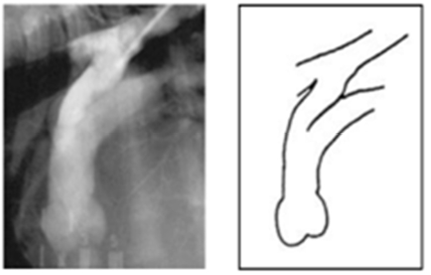

PDA Type

뾰족 + 얇음

ⅡB뭉툭 + 두툼

ⅡA두툼 + 짧음

관이 길다

가장 심각